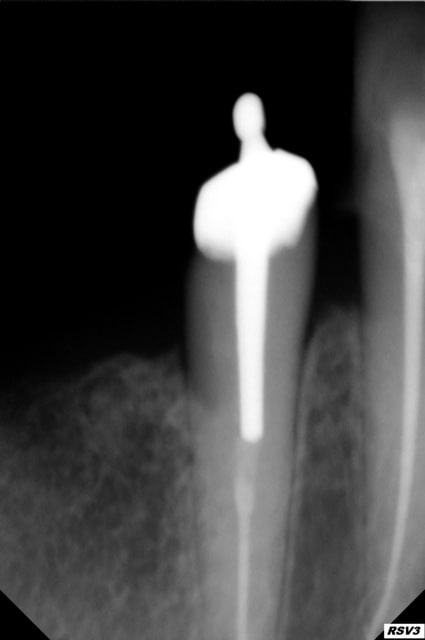

Je n'arrive pas a enlever ce putain de tenon a la base il s agissait

d'un attachement axial (boule ) que je voulais enlever pour faire un inlay core en suite 6 couronnes liées avec 2 attachements extra coronaires.

et les radios à la demande générale!